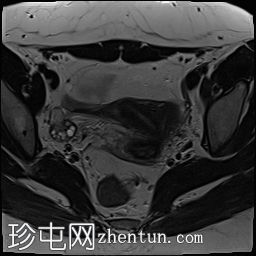

冠状位

斜位T2加权像

子宫外底轮廓清晰,肌层较厚,将子宫内膜腔分隔成两个腔,纤维层较薄,向下延伸至宫颈外口。子宫内膜厚度正常,两个子宫腔交界区清晰,未见明显的实性局灶性病变。

卵巢卵泡形态正常,可见多个小卵泡,主要位于卵巢周边,无优势卵泡。未见实性或囊性肿块。

膀胱MRI表现正常。

未见盆腔软组织肿块或淋巴结肿大。

未见明显盆腔游离积液。

本病例展示了典型的纵隔子宫影像学表现:增厚的肌层隔膜将子宫内膜腔分隔成两个腔,并有一层薄的纤维隔膜延伸至子宫颈外口水平,符合完全纵隔子宫的特征。

纵隔子宫是最常见的先天性子宫畸形,可能导致流产率升高。

磁共振成像(MRI)是目前首选的影像学检查方法。

在MRI图像上,纵隔子宫通常大小正常,但每个子宫腔的形态均小于正常子宫腔。

隔膜可能由纤维组织(T2信号低)、肌层组织(中等信号)或两者共同构成,如本病例所示。